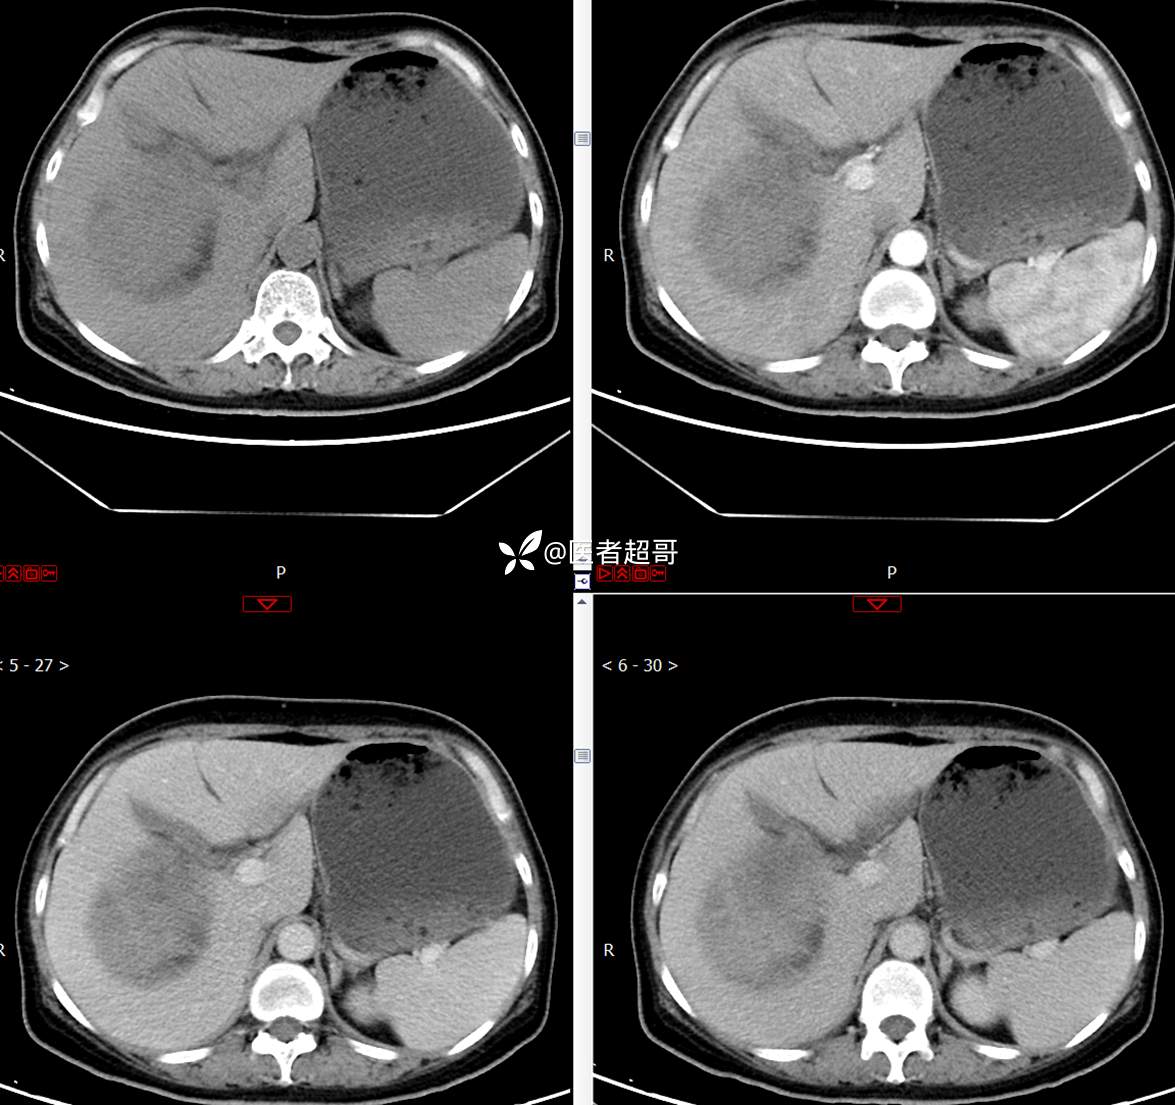

现病史:患者1周余前发现右上腹有一半球形巨大肿物,约18cm*15cm大小,既往贫血病史3年余,诉乏力,易疲劳,偶有头晕,活动后心悸,无腹痛、腹胀,无恶心、呕吐,无尿频、尿急、尿痛,无排尿困难,患者为求进一步治疗,来我院消化内科就诊,门诊行肝.胆.胰.脾.肾彩超示:右肾上部囊实性占位,范围约18.0cm×11.7cm×16.4cm,边界清,形态规则,建议进一步检查,腹膜后实性结节。我科遂以“肾肿物”收治入院,患者自发病以来,神志清、精神可,睡眠、饮食可,二便正常,体重、体力略有下降。